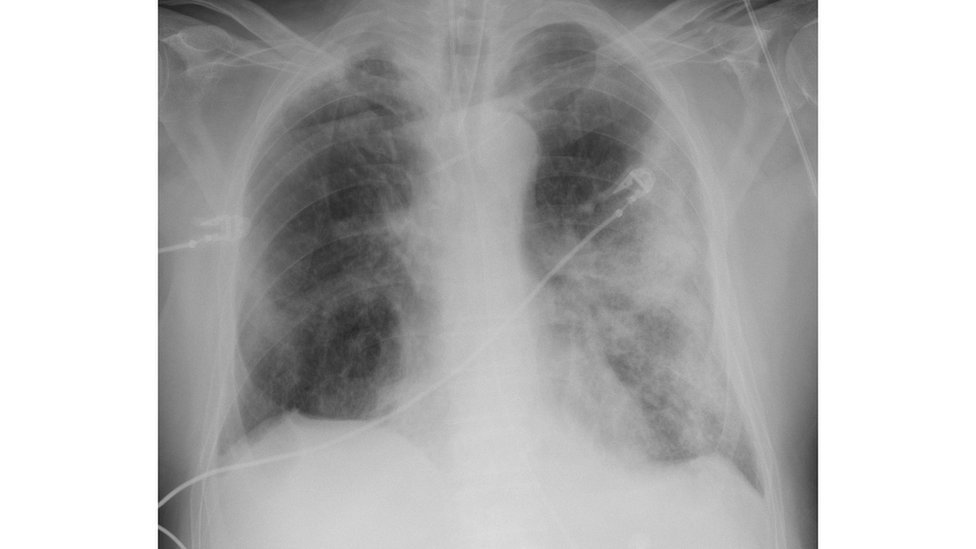

Coronavirus O Que Os Cientistas Ja Descobriram Sobre A Covid 19 Nos Seus 6 Primeiros Meses Bbc News Brasil

Coronavirus O Que Os Cientistas Ja Descobriram Sobre A Covid 19 Nos Seus 6 Primeiros Meses Noticias R7 Saude